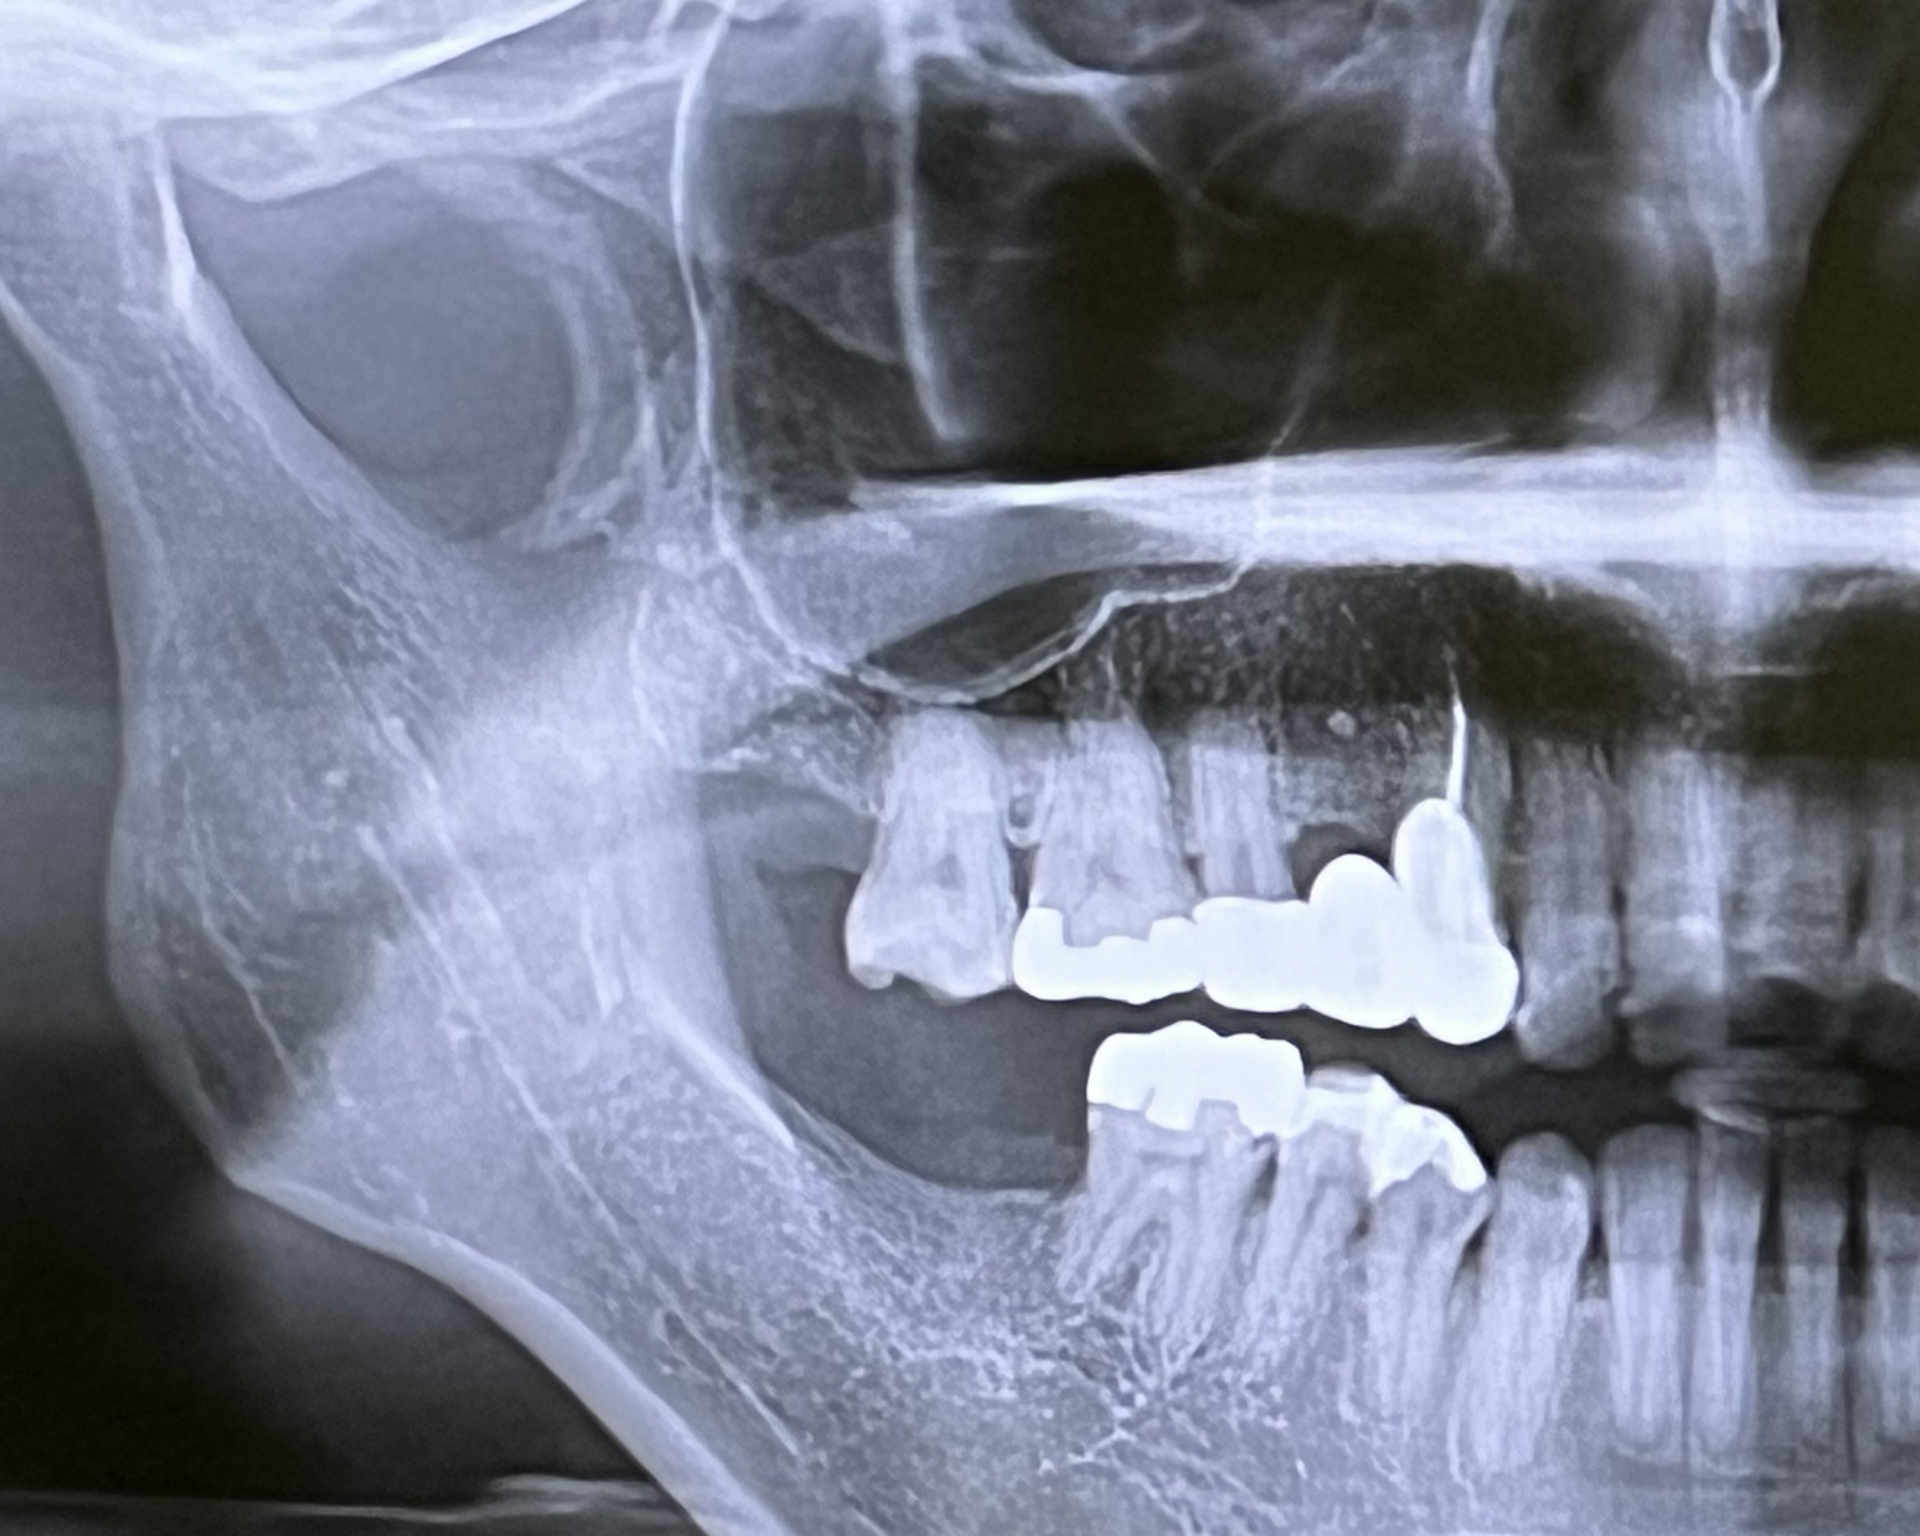

次にレントゲン写真で歯の根っこや歯を支えている骨の状態を調べます。レントゲン写真では、歯周病で骨が溶けてしまっていないか、隠れた虫歯がないかなど、細かいところまで確認します。